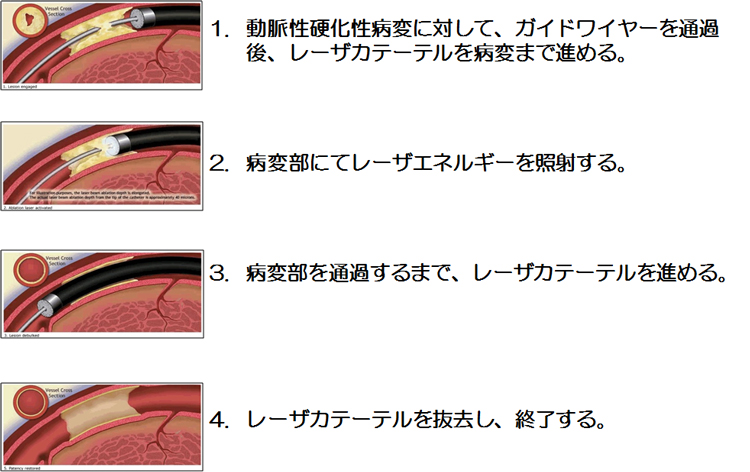

エキシマレーザー治療

当科では2014年から心筋梗塞などの症例に対してELCA(エキシマレーザー)を積極的に併用しています。エキシマレーザーとは非熱的な物理的エネルギー(光子エネルギー)が分子結合に直接作用して分解することで、血栓やプラークを蒸散、除去することができます。他のレーザー治療と比較して熱発生がなく、末梢塞栓の発生率が極めて低いといわれています。心筋梗塞の症例における血栓性病変や柔らかい脂肪組織を主体としたプラークへ使用することでステント留置後の冠動脈の目詰まりを予防することや慢性閉塞病変の硬い部位を安全に除去することが期待されています。ELCAは全国でも施行できる施設が少ない高度医療であり、当科では日本有数の施行症例数を誇っています。